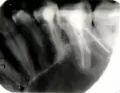

Я пришла с просьбой что-то сделать с болью между шестым и седьмым нижними зубами, точнее был разрушен шестой зуб ближе к седьмому. Врач мне говорит, что это десна дает боль. Она мне поставила на шестой и седьмой зубы пломбы, а щель оставила. Боль сильная только тогда, когда попадает в щель сладкое, она не ноющая, а резко стреляет, пока не начну полоскать водой.

Скажите, пожалуйста, это нерв или десна дает боль такую?

Тут конечно может быть и то и другое.

Десневой карман приносит массу проблем и также сопровождается острой болью. Также возможно слегка оголился корень зуба.

Но более корректно можно сказать только при осмотре и рентген снимке.